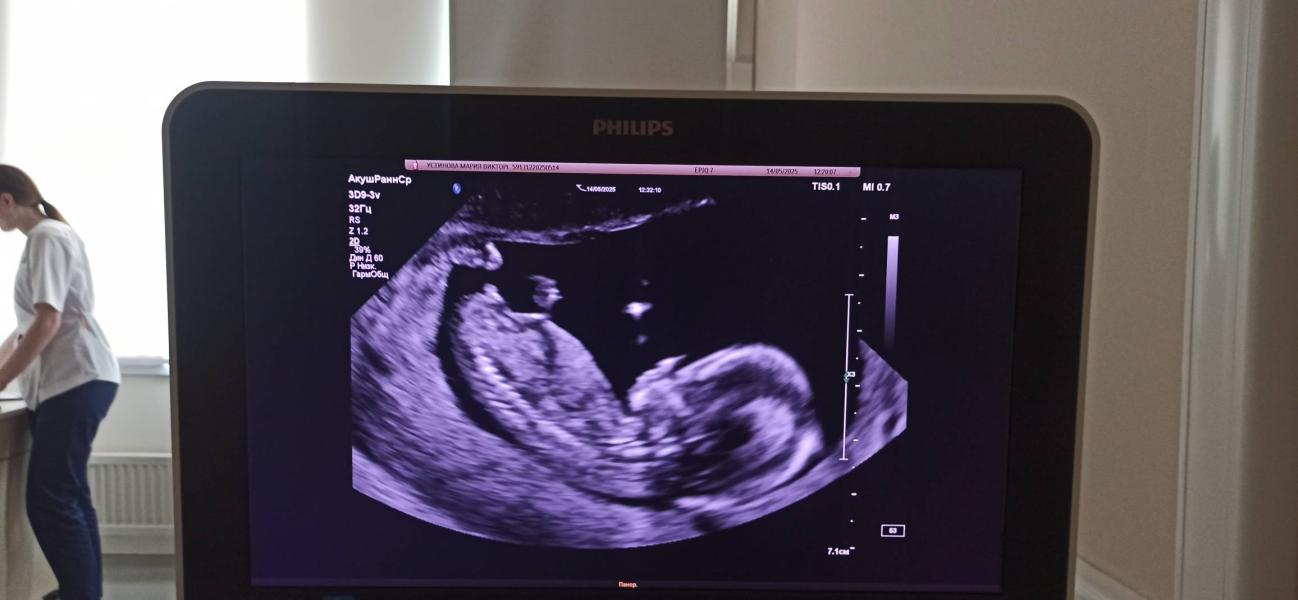

Maria ·Мама двоих (6 лет, 7 лет), ждёт третьего

Девы, кого видите?

Ставлю на девочку, угол между половым бугорком и позвоночником как у моей по снимкам)

У мальчика бугорок наверх торчит

Девочка по бугорку

Девочка,у мальчиков бугорок к верху торчит